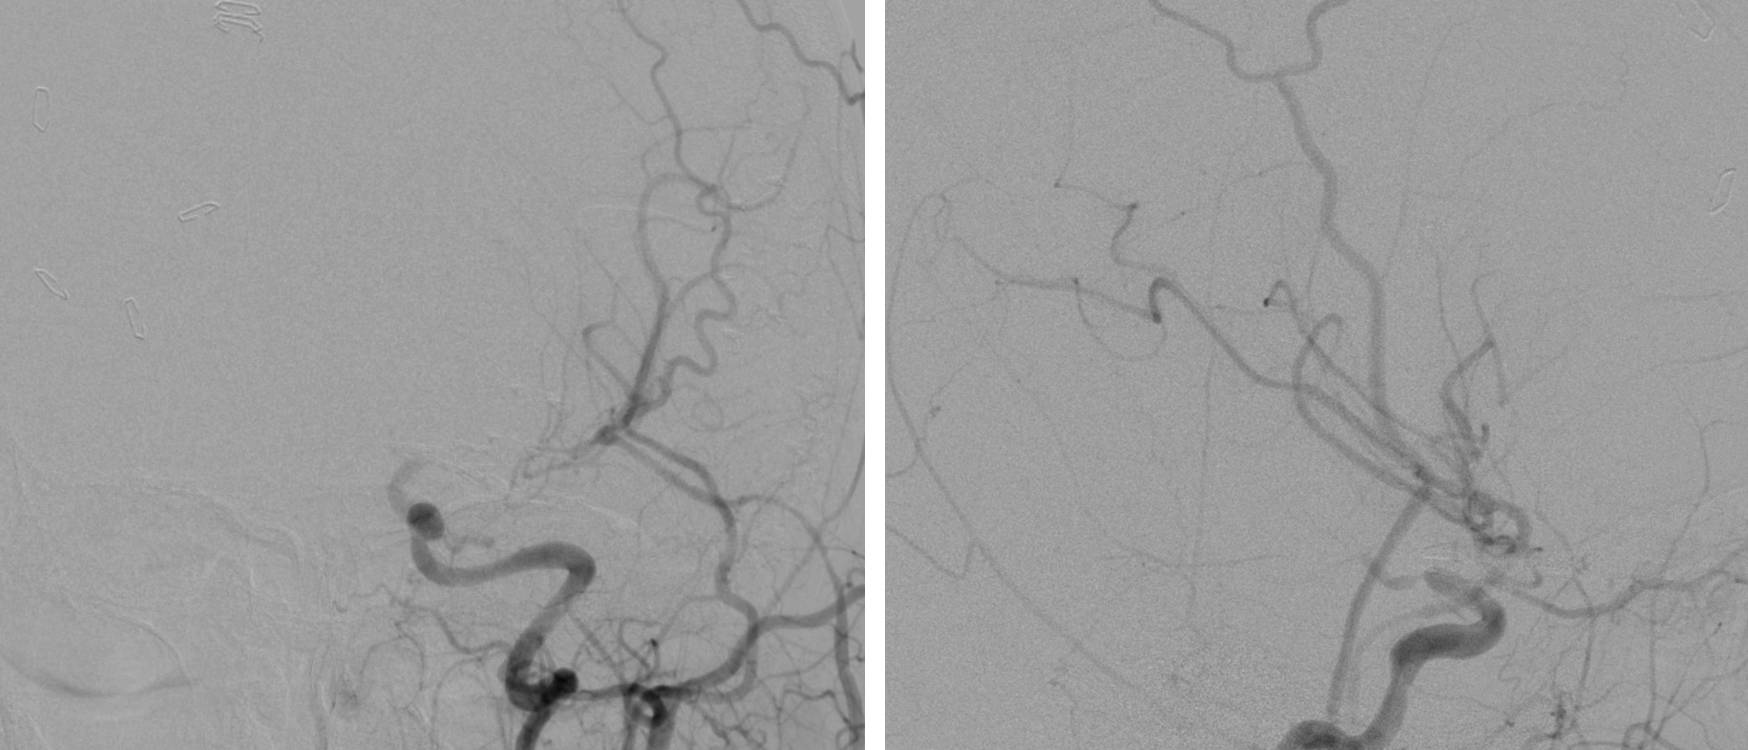

图1. 左侧颈内动脉分叉部动脉瘤,大小6cm,伴钙化和部分血栓形成,传统的显微手术夹闭不可行。治疗方案为:颅外段ICA-M2的高流量搭桥、结扎脉络前动脉以远的ICA(Hunter方式)、阻断同侧A1逆流进入瘤腔的血流。后文有展示本例术中情况的图片。

图11. 图1所示患者的术后血管造影证实动脉瘤已被孤立不显影,同时桥血管血流通畅。